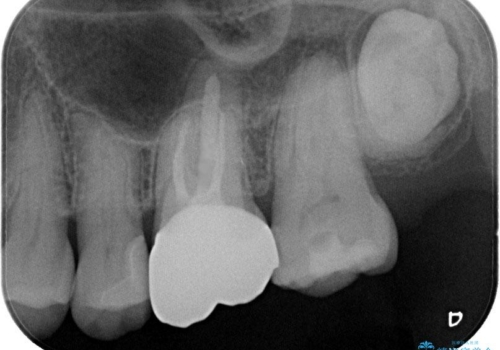

金属をセラミックにしたい、根管治療も行ったケース

左上6の金属のかぶせものをセラミックにかえるにあたり、根管治療からやり直しています。

左上5の虫歯もセラミックインレーにて修復しました。

基礎工事と同じで、歯の治療においても見えるところを白くきれいにするだけではなく、根管治療をしっかり行うこともとても大切です。

患者様にはとても満足していただけて、順次、他のところも治療していく予定です。